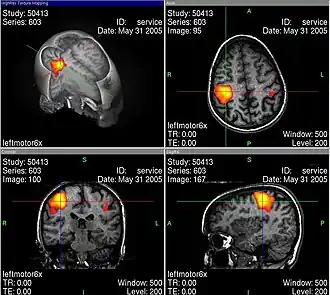

L’usage de l’imagerie cérébrale dans des programmes de recherche en neuropsychologie nécessite de bien maîtriser tous les artefacts et biais statistiques possibles, par exemple lors de l’IRMf en faisant des moyennes spatiales, temporelles et interindividuelles. La base de cet examen est de déterminer des corrélations entre certaines tâches mentales (langage, attention, mémoire…) et des activations spécifiques de zones du cerveau[33].

Les activités électriques du cerveau conduisent à des variations de tension électrique à la surface de la tête, que l'on peut enregistrer avec des appareils convenables. Les neurosciences cognitives actuelles reposent très largement sur le procédé d'imagerie par résonance magnétique fonctionnelle (IRMf). En même temps, ce genre de méthode soulève déjà une série de questions éthiques. Au moyen de l'IRMf, l'activité dans le cerveau peut être mesurée avec une bonne définition spatiale et temporelle. Cette technique conduit à des problèmes éthiques en particulier quand on trouve au moins grossièrement des corrélations entre l'activité neuronale et l'état conscient du sujet. Comment se comporter quand on sait par des méthodes neurologiques, et non par ce qu'elle en dit, qu'une personne pense à quelque chose ou le sent ?

Les images d'IRMf bien connues (voir par exemple ci-contre) sont toujours interprétées selon des modèles qui en permettent la lisibilité. Pendant une tâche cognitive, le cerveau est constamment actif dans un grand volume, et il faut trier pour obtenir des images significatives, dépourvues de toutes les activités apparemment secondaires. Ce genre de tri se fait avec une méthode de soustraction : par exemple si l'on s'intéresse à une tâche cognitive K, alors on mesure l'activité du cerveau dans une situation S1 dans laquelle K est accomplie. Ensuite, on mesure l’activité dans une situation de contrôle S2 qui ressemble à S1, mais qui n'a a priori rien à voir avec la tâche K. Finalement, on soustrait les activités mesurées dans S2 de celles mesurées dans S1, pour voir les activités corrélées avec la tâche K de façon spécifique. Illes souligne qu'il faut toujours garder en tête ces aspects interprétatifs, ce qui peut facilement passer inaperçu devant un tribunal, parce que les juristes n'ont probablement aucune compétence en neurologie.

Turhan Canli explique : « L'image d'un type d'activité basée sur une étude de mauvaise qualité ne peut pas être visuellement distinguée de celle d'une étude exemplaire. On doit être un habile spécialiste pour éventuellement remarquer la différence. C'est là que réside le grand danger d'abus des données d'imagerie auprès d'un public non éduqué, comme le jury d'une cour d'assises. Si l'on regarde les images, on peut facilement oublier qu'elles représentent des déductions statistiques et jamais une vérité absolue[35] ».